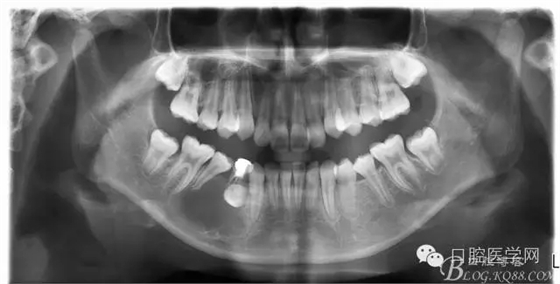

查:右側(cè)第二前磨牙第一乳磨牙恒尖牙頰側(cè)前庭溝隆起,捫有乒乓球感。曲斷及CT示:右側(cè)第二前磨牙第一乳磨牙恒尖牙根尖區(qū)有一囊腫,頰舌側(cè)骨板極薄,牙根無吸收,第二前磨牙牙根位于囊腫中,第一雙尖牙牙冠遠(yuǎn)中水平向阻生,牙冠位于囊腫中。經(jīng)協(xié)議:手術(shù)摘除創(chuàng)傷大,同意開創(chuàng)引流保守治療。

術(shù)后一個月 三個月 五個月 八個月 拔除第一雙尖牙后曲斷片:

正畸查:替牙合。第一恒磨牙中性合。上牙弓尖圓型下牙弓方圓型。前牙覆合3度覆蓋7.5mm。下前牙咬到上舌側(cè)牙齦。上頜擁擠4.0mm,下頜擁擠